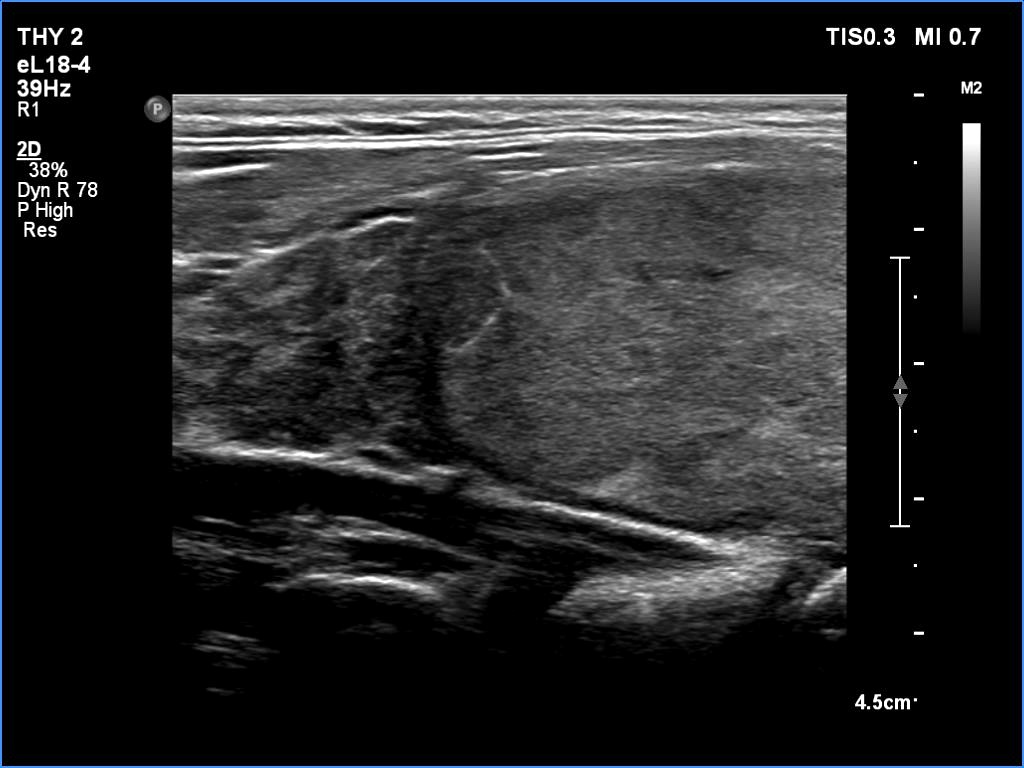

The echogenicity of the nodule - case 365 (ultrasonographic picture 6)

Five years after the first examination

Left lobe, longitudinal scan. Compared with the non-nodular part, the lesion is more echoic.